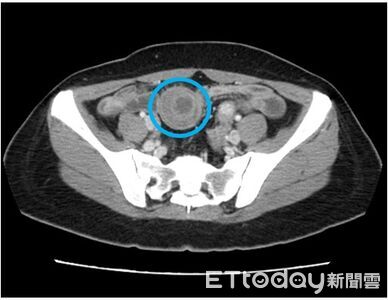

一位45歲的王姓女子一個多月以來飽受腹部疼痛與胃痛困擾,經診斷為小腸套疊,套疊得如望遠鏡,卻驚人發現腸套疊的元凶,竟是小腸黏膜下層一顆三公分罕見腫瘤。平等澄清醫院一般外科王志浩醫師表示,腫瘤因其生長位置與特性,常會引發嚴重的腸套疊,若不及時處理,恐引發腸道缺血壞死或穿孔危及生命。 《詳全文...》